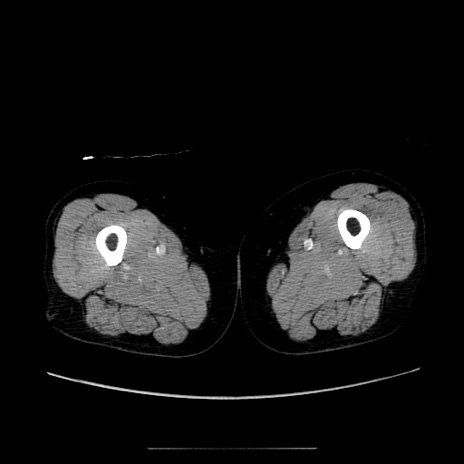

症例5(横断像)

【症例】70歳代女性

【主訴】お腹が張る

【現病歴】1週間くらい前から腹部膨満の自覚あり。昨日夜から増悪したため、本日救急外来受診。

【身体所見】意識清明、BT 36.5℃、BP 165/106mmHg、HR 80bpm、SpO2 98%、腹部:膨満、軟、自発痛・圧痛なし、触診にて不快感あり、腸蠕動音:減弱

【データ】WBC 12600、CRP 1.04